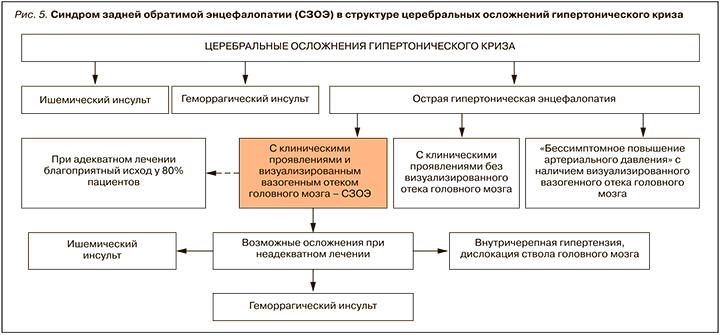

АГ относится к основным факторам риска развития сосудистых осложнений, а головной мозг – это одна из главных мишеней при этом заболевании [24]. Поражение мозга при АГ представлено как хроническими, так и острыми состояниями; последние включают острую гипертоническую энцефалопатию (код МКБ 10 – I67.4), одним из проявлений которой может быть СЗОЭ (рис. 5).

Несвоевременная диагностика и неадекватное лечение СЗОЭ может сопровождаться развитием стойких осложнений в виде ишемического или геморрагического инсульта, дислокации ствола головного мозга, а также летального исхода. По данным Hefzy H.M. et al. [17], неблагоприятный исход СЗОЭ отмечается в 20–25% случаев и в большинстве наблюдений обусловлен усугублением фонового заболевания, включая развитие/нарастание полиорганной недостаточности.